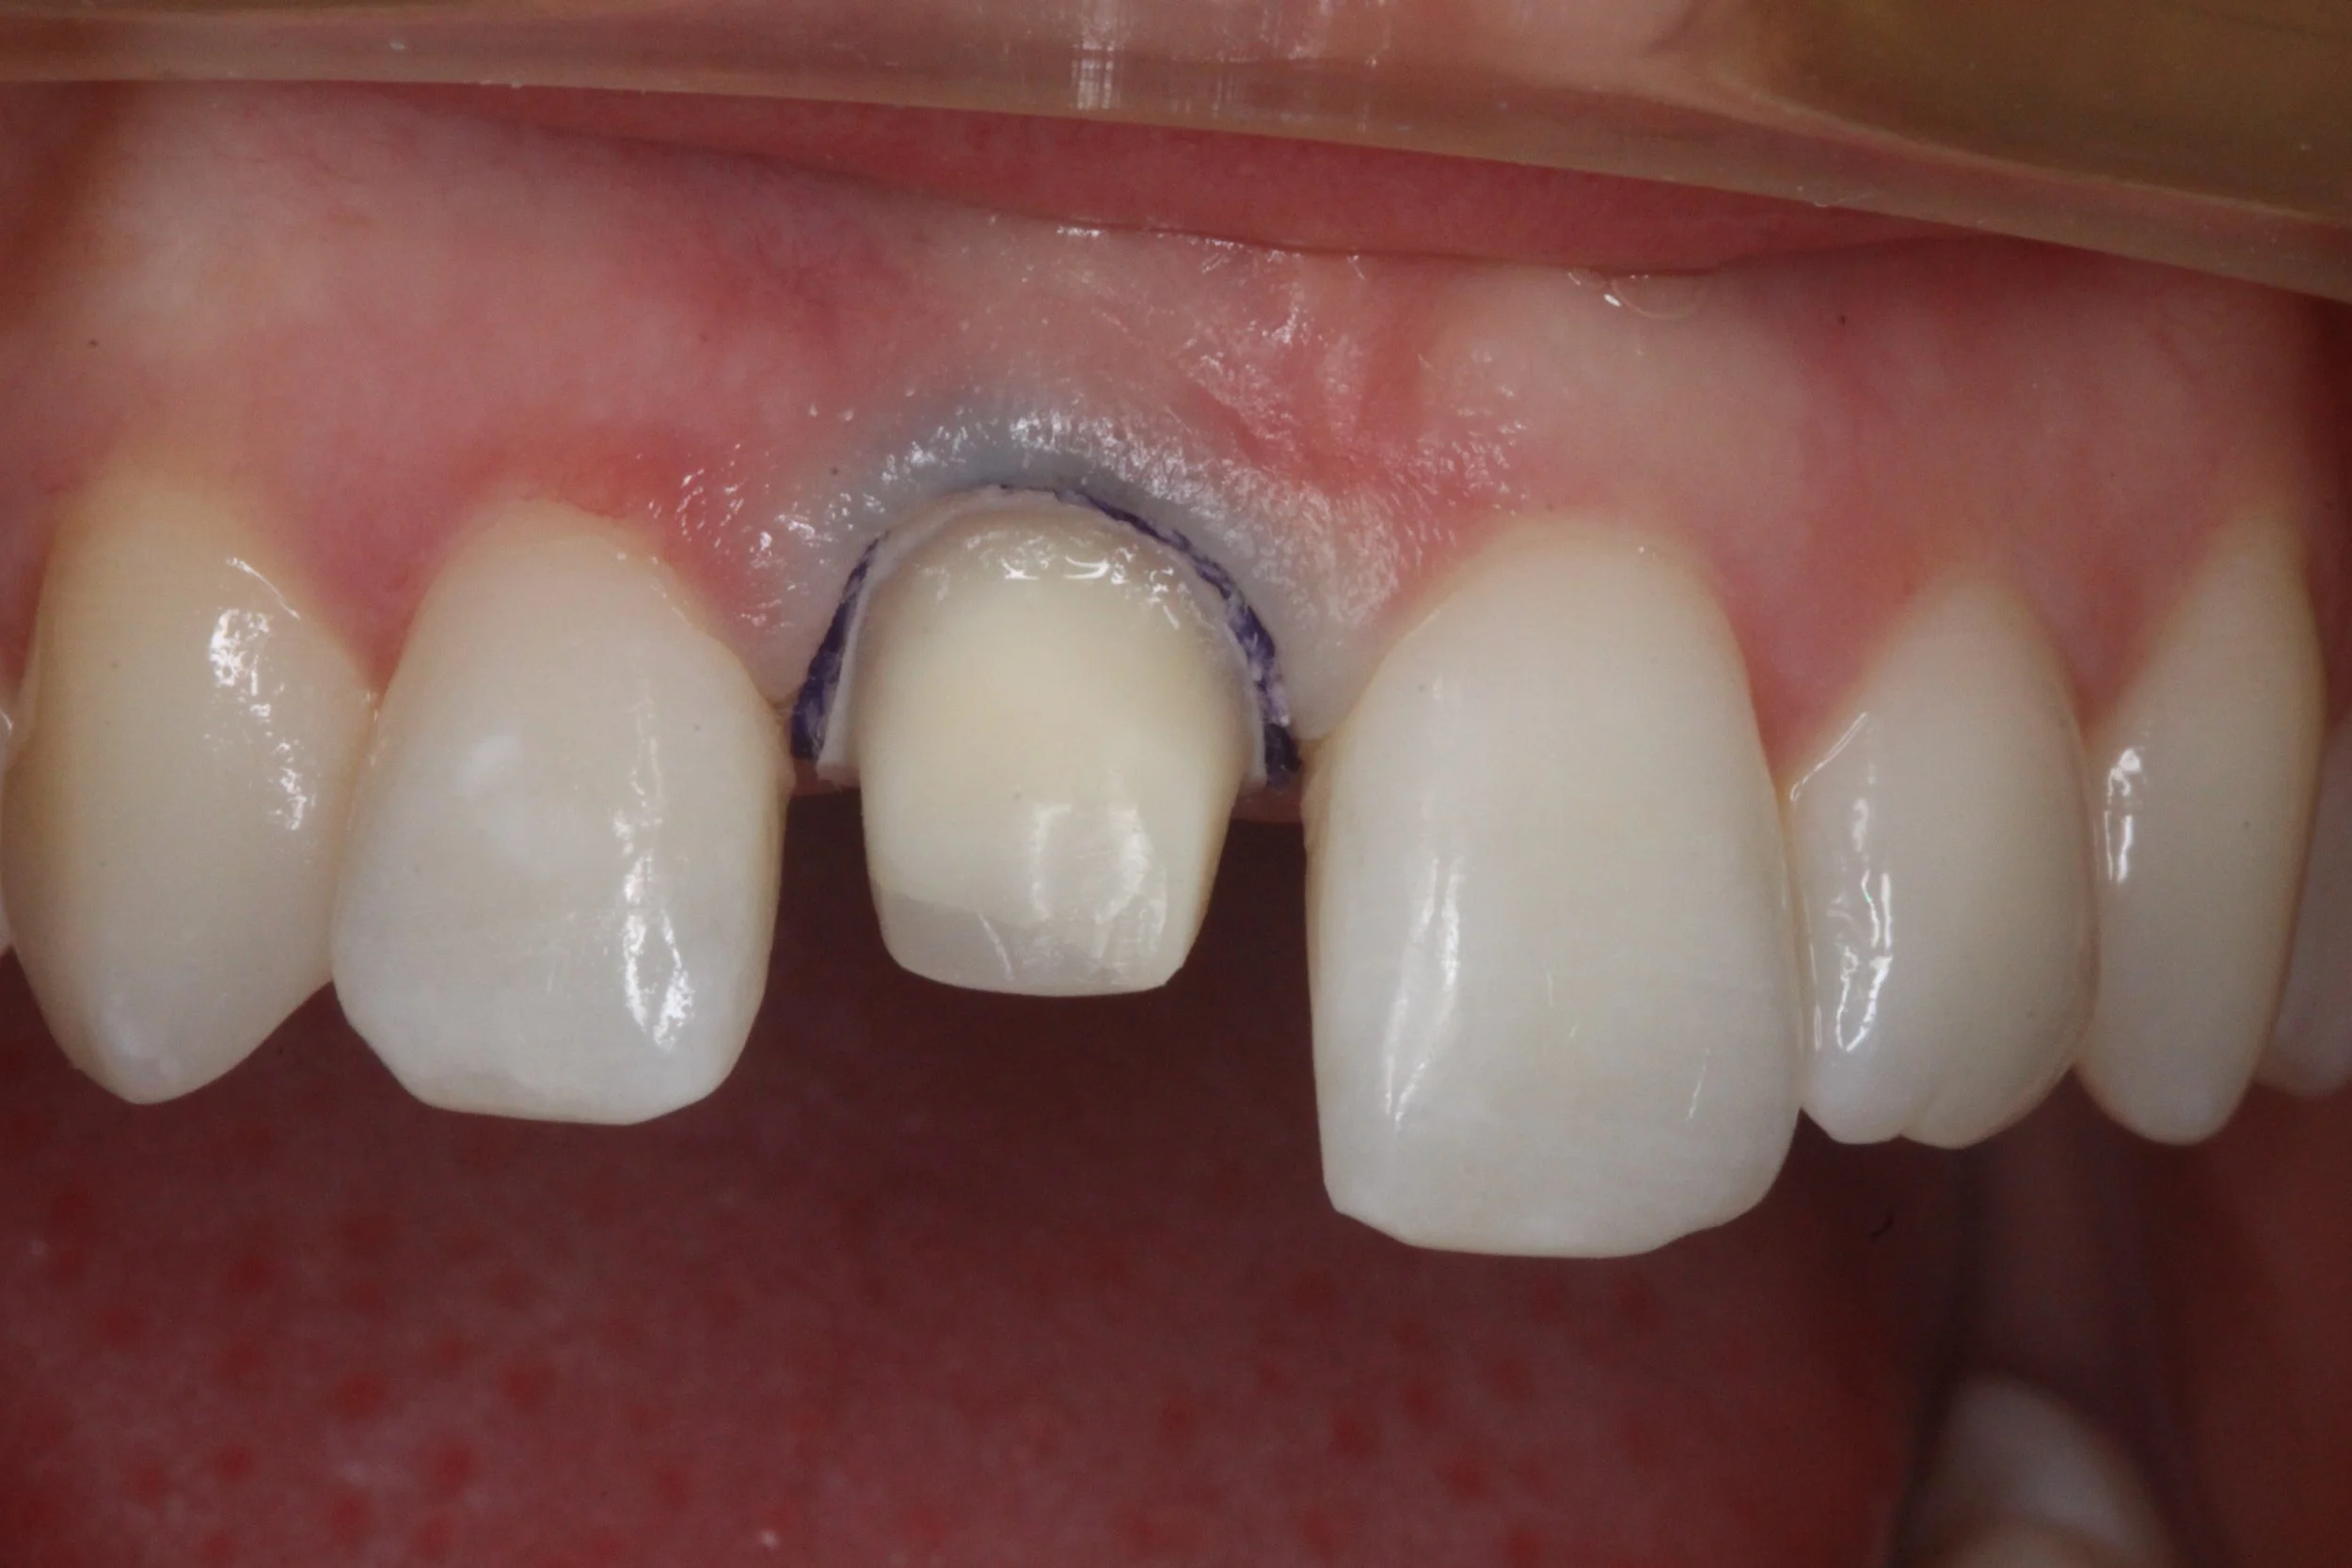

Fixed pros